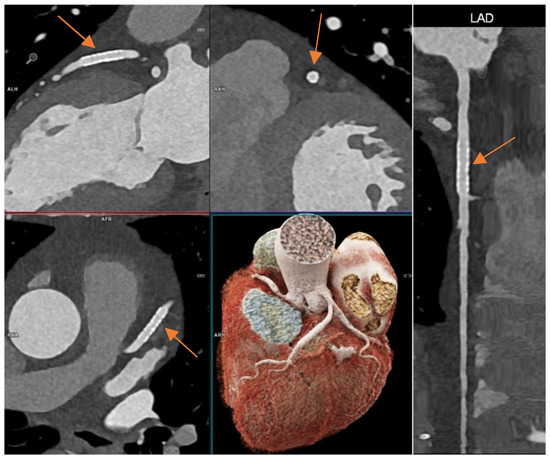

3.5. Image Quality, Assessability and CNR of the Three Main Vessels

3.7. Diagnostic Performance in the Subgroup with ICA as Reference Standard

4. Discussion